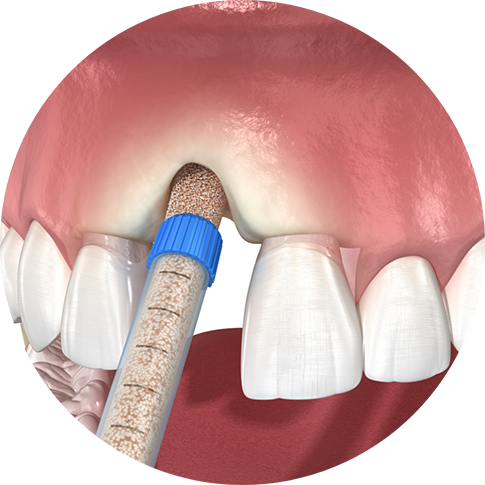

How Does Bone Grafting Work?

The bone grafting process is normally a very standard and straightforward procedure. While there are different types of grafts, as well as different sources for the grafting material, the order of operations is simple. After your mouth has been numbed, an incision is made to access the bone that needs grafting. After this area is cleared of any diseased tissue and sanitized, the graft is applied.

Over time, the grafted material fuses with nearby bone tissue and becomes integrated, becoming a natural part of your jaw. This healing period can take anywhere from several months to a year, but the end result is durable, restored bone tissue that benefits your jaw’s health!